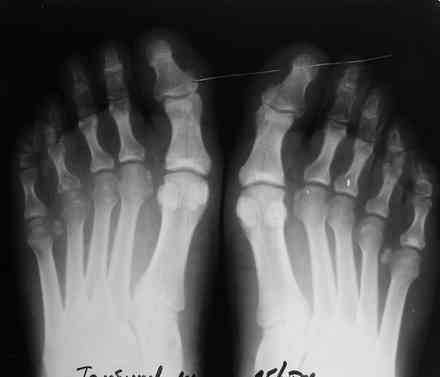

Уважаемые коллеги. Помогите определиться с диагнозом. Мужчина 28 лет обратился с жалобами на боль в правой стопе, усиливающиеся с утра "пока не расходишься".

Боль беспокоит на протяжении 4 мес, Имеется незначительная припухлость. болезненность при пальпации головок 4,5 плюсневых костей справа, кожа не измененена. Лабораторные данные в пределах нормы, хронических инфекций нет. рентгенологически имеется остеопороз головок 4,5 плюсневых костей справа.

Здравствуйте Максим! Вполне возможно, что это остеохондропатия по типу болезни Келлера 2 в начальной стадии.

там же вроде II -III плюсневые поражаются, чаще у молодых женщин.

-Симметричное поражение

очень напоминает ревматоидный полиартрит, направьте к ревматологам. как ортопеду причин для вмешательств пока нет.

в том то и дело, что асимметричное, только головки 4,5 справа, все остальное не беспокоит